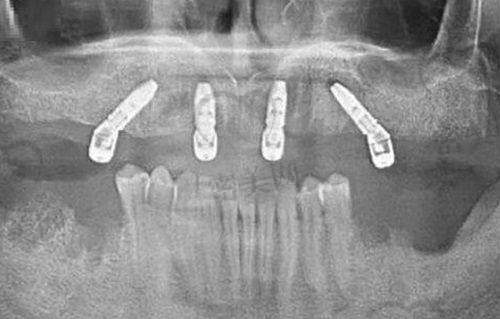

王安文院长:擅长复杂类牙齿种植技术,如穿颧穿翼种植术及全口种植(All-on-4)。

特色诊疗服务涵盖:All-on-4种植、数字化种植导航、陶瓷贴面微笑设计、儿童行为管理下齿科治疗等。